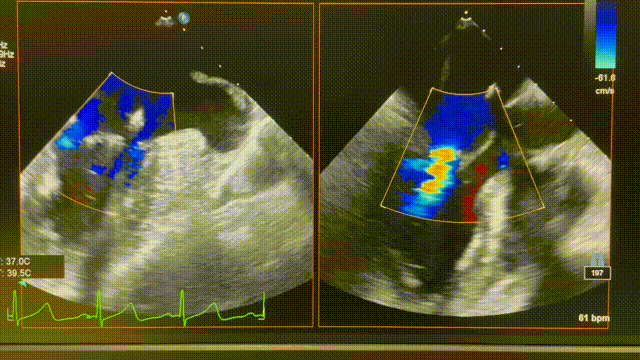

图片

图2 术前心超图。

图3 术后心超图。